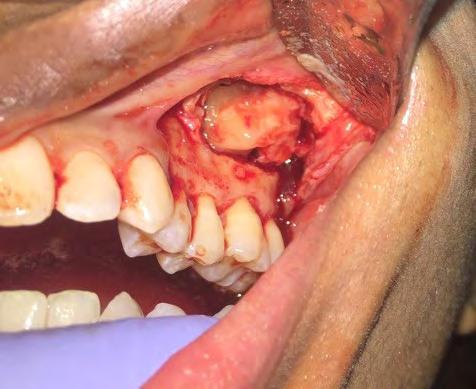

28 An Osteoma Embedding an Ectopic Wisdom Tooth within the Maxillary Sinus A Rare

Kayvan Fathimani, D.D.S., FACS, FRCD(C), FIBCSOMS

Unerupted third molar within maxillary sinus coexisting with maxillary sinus osteoma is extremely rare pathologic finding. Author describes treating patient who presented with this anomaly.

Occurrence